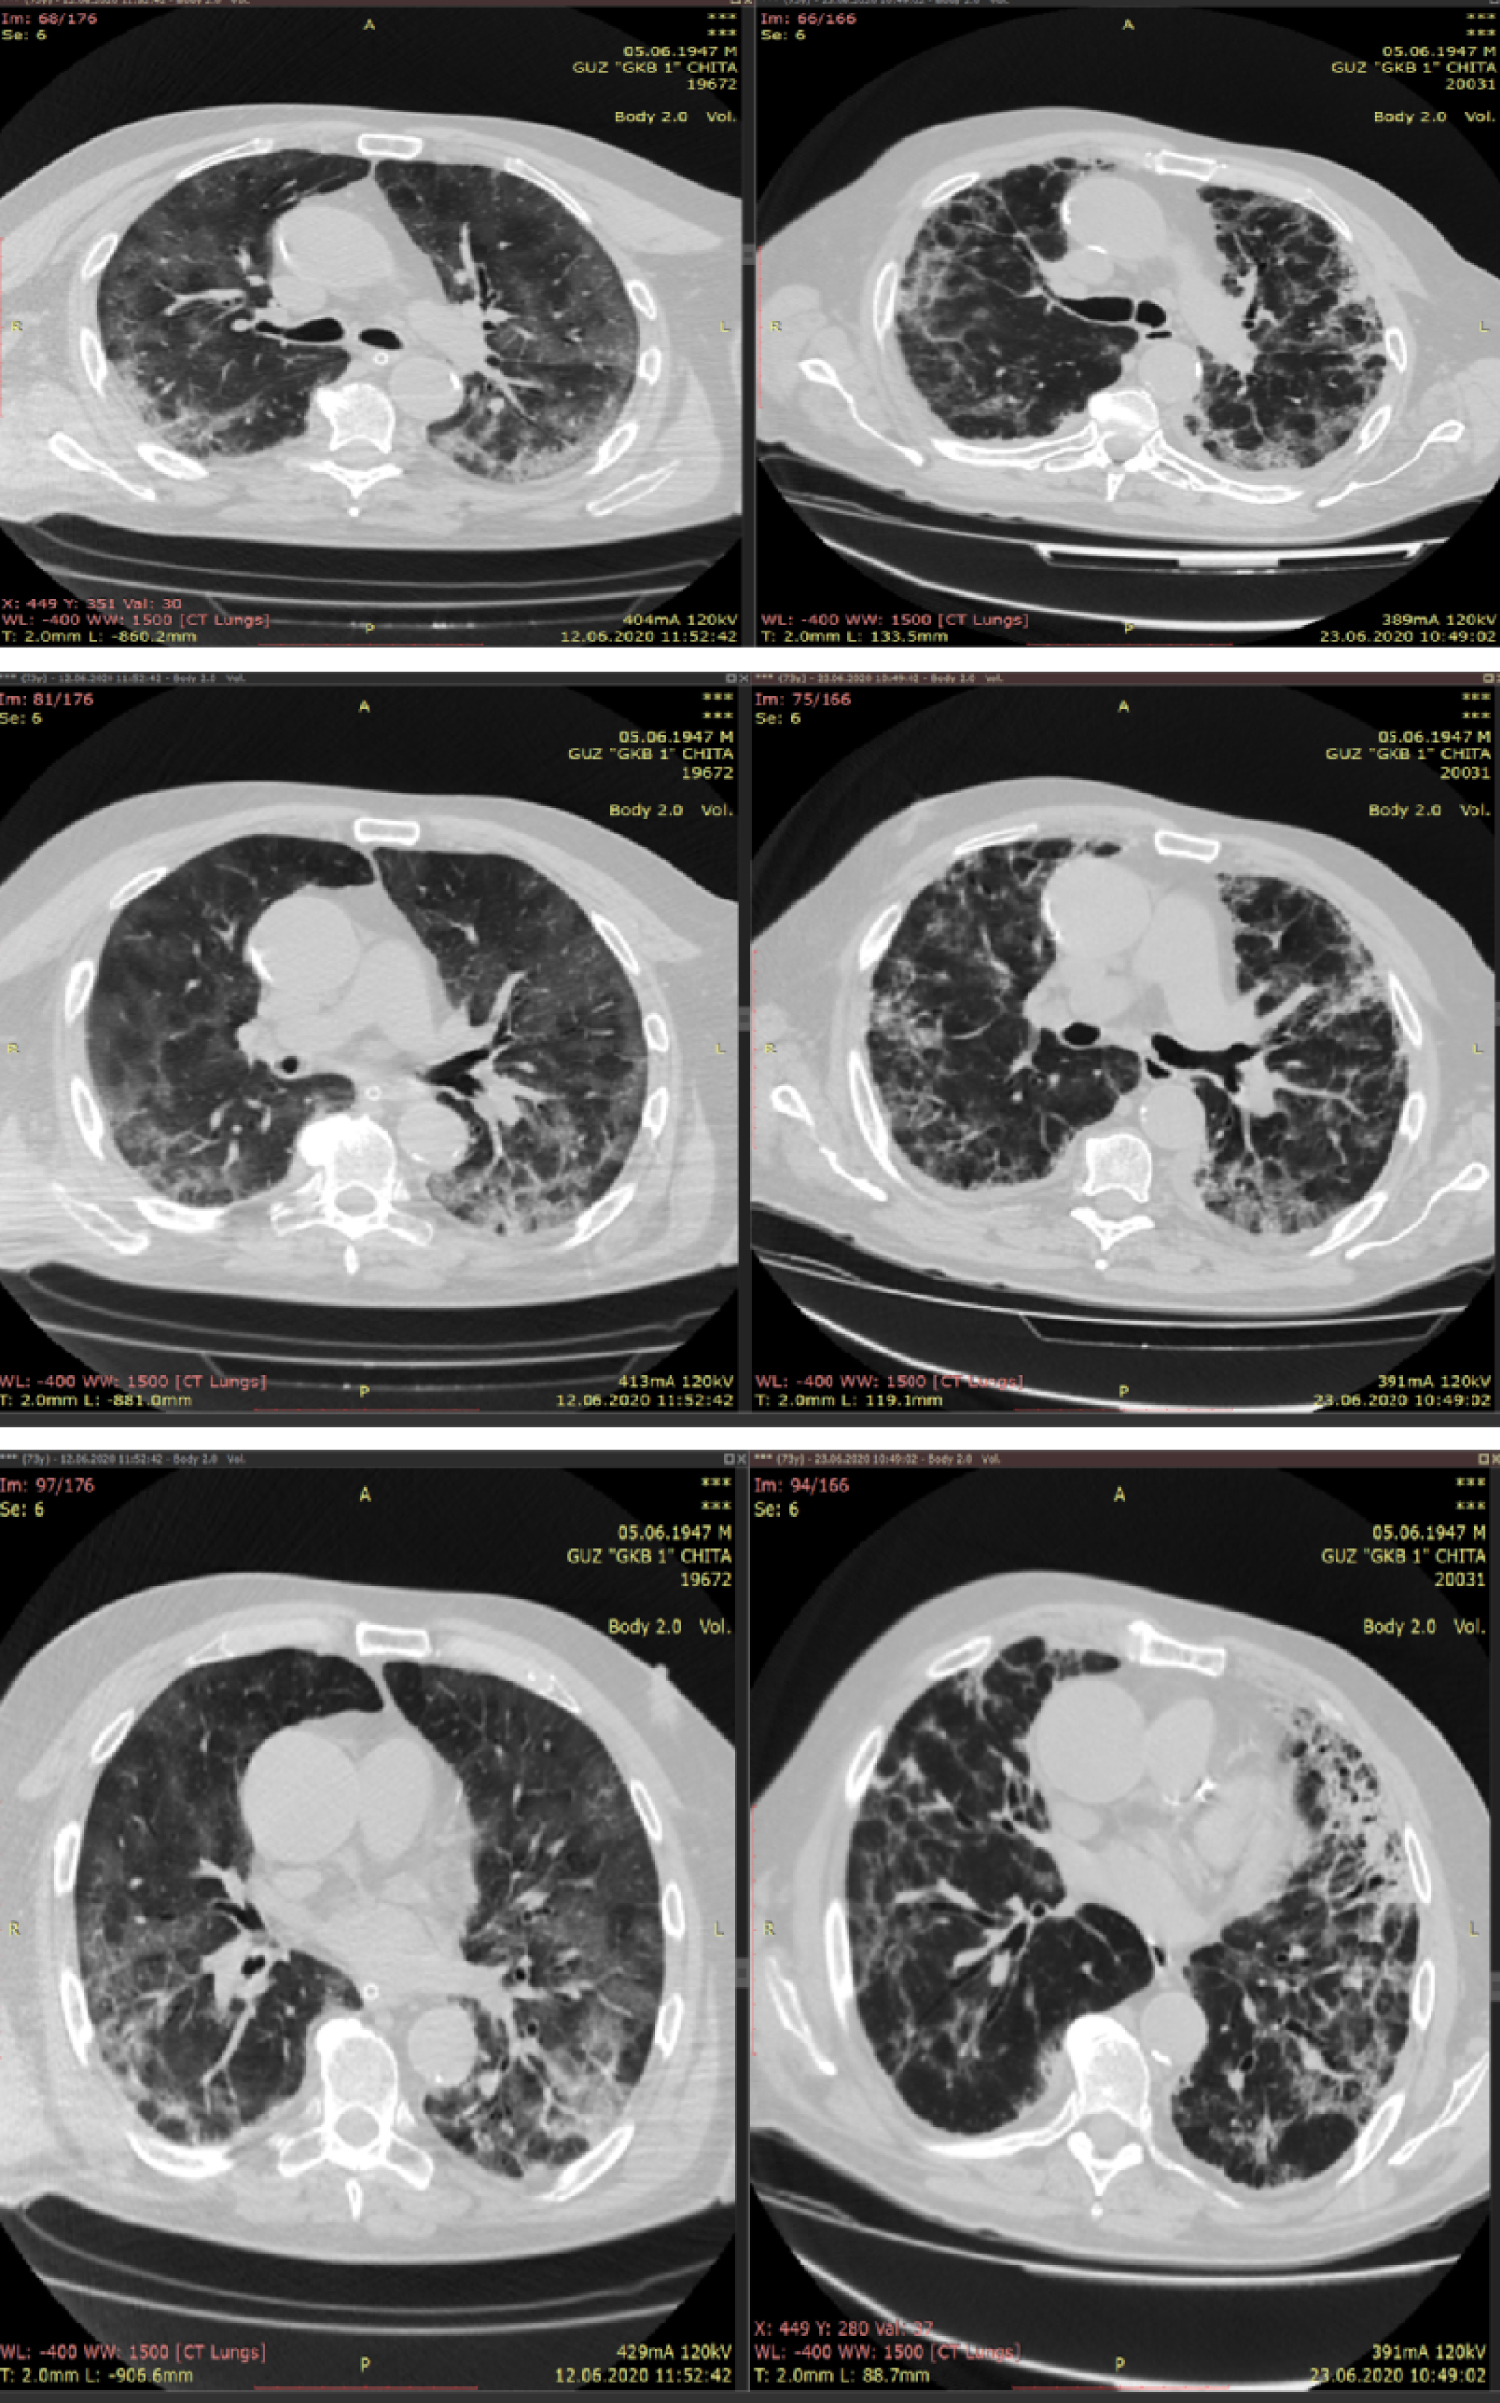

On June 14, he developed progressively worsening hypoxemic respiratory failure. The patient was managed by intermittent prone positioning, fluid restriction, and mechanical ventilation through the tracheostomy. Laboratory studies revealed rising serum inflammatory markers (Table 1). Repeated CT scan showed large area of ground-glass opacity with irregular density in the subpleural regions of both lungs, with 'crazy-paving sign, predominantly in the lower lobes, multiple patchy consolidations were apparent in both lungs, with air bronchus-charging sign and thickening of the pulmonary interstitium surrounding the lesions (Figure 1).

Figure 1: Chest CT scan on 12.06.2020 shows large areas of ground-glass opacity with irregular density in the subpleural regions of both lungs, with 'crazy-paving sign', predominantly in the lower lobes, multiple patchy consolidations were apparent in both lungs, with air bronchus-charging sign and thickening of the pulmonary interstitium surrounding the lesions. View Figure 1